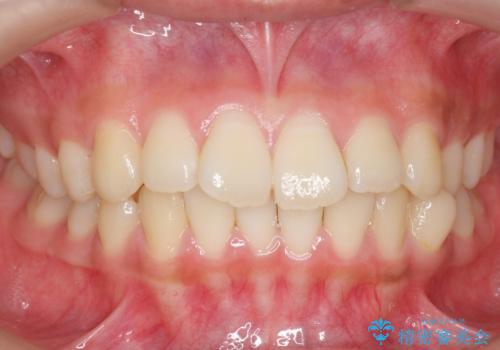

前歯のがたつき 部分矯正でコストダウンしながら、かみ合わせも治療

- 前歯のがたつきを気にして来院。

左下の小臼歯が捻転し、反対咬合になっていました。

先にワイヤーで部分矯正を行ってから、インビザラインの部分矯正を行いました。